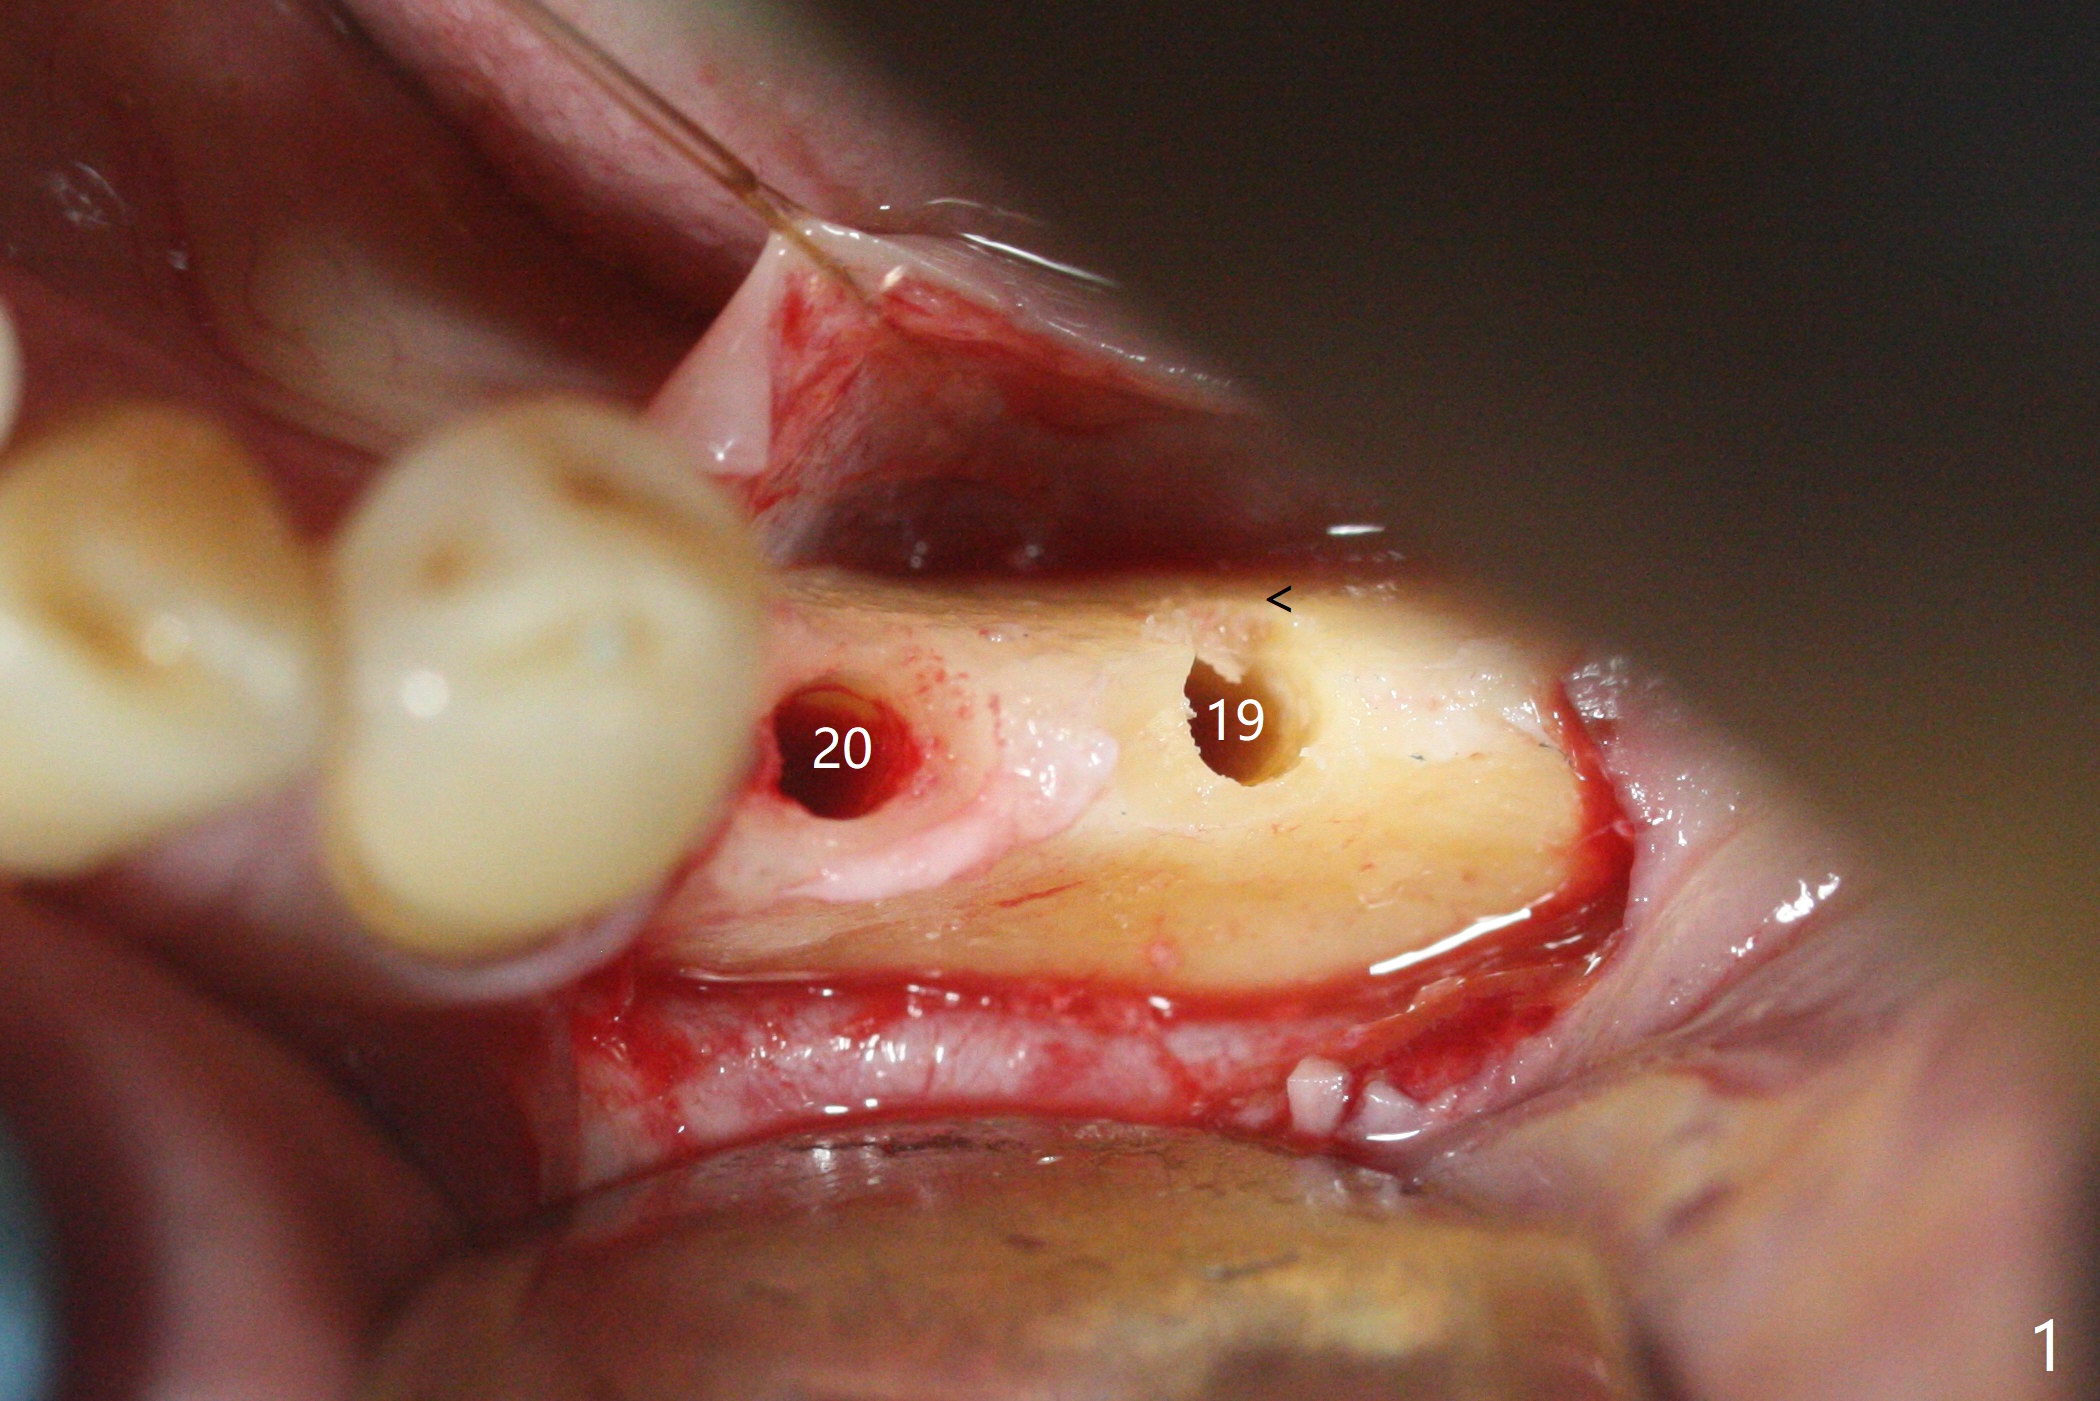

左下第一磨牙(#19)牙槽嵴狭窄,2.2毫米钻头完成导板钻洞后,舌侧骨板开始破裂(图一:<),打消牙槽嵴劈开术念头,放置2.5x8.5毫米一段式植体(图二(8.5毫米是最短植体)),好像离下齿槽神经管还有一定距离,适当植入深些(图四:箭头,15Ncm)。右下中切牙缺牙区牙槽嵴也十分狭窄(图四),最后不得不徒手植入2x8.5毫米植体(图五,六,25Ncm)。如果按设计植入2x12毫米植体,颊侧,或者舌侧骨板更容易穿孔。术后3.5月牙槽嵴下降(图七:箭头),可能术中那里压力太大,今后牙槽嵴钻洞要大。24号牙根尖阴影(图七),完成根管治疗(图八)。19牙位牙槽嵴吸收也严重(图九)。其实术后4个月19牙位牙槽嵴吸收并不严重(图十一)。